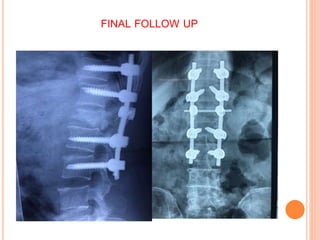

FINAL FOLLOW UP X-RAY

FINAL FOLLOW UP